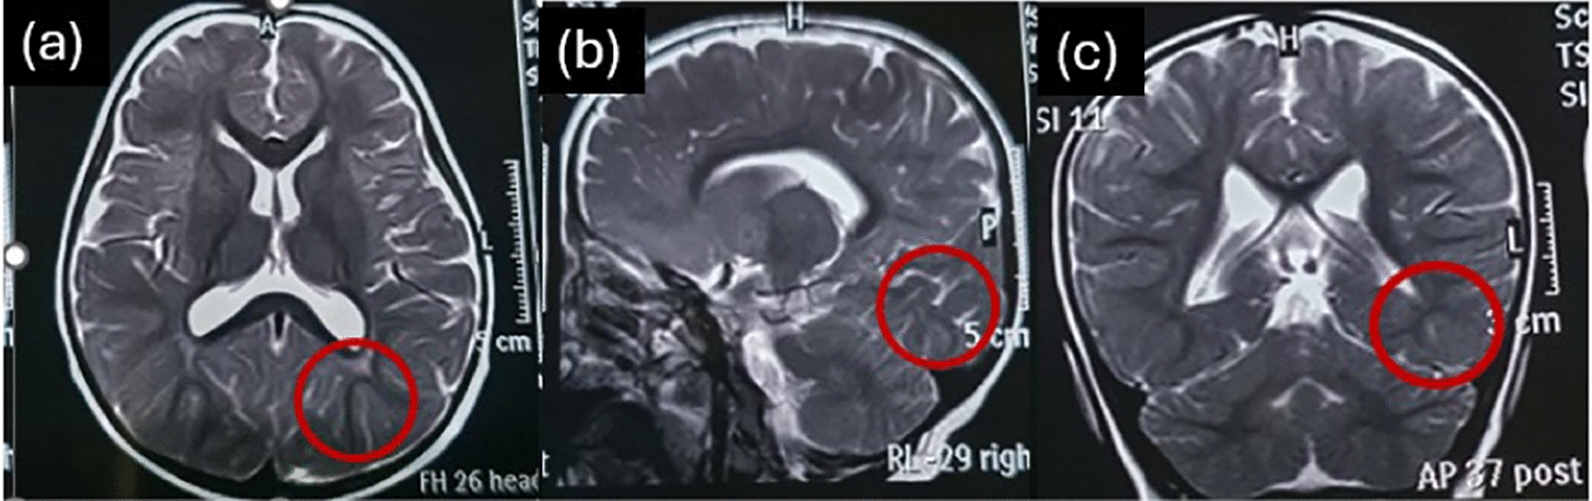

The brain MRI report at the age of 2 years showed mild dilation of sulci of the occipital lobe and mild increased signals of the white matter adjacent to trigone of lateral ventricle (Fig. 1). Dysrhythmic discharges in both hemispheres were noted by electroencephalogram (EEG) findings when she was 1 year old, and pirimidon was prescribed by a pediatric neurologist. The MRI report at the age of 2 years was normal but somewhat smoggy, addressed by a pediatric neurologist. EEGs were repeated at least twice a year to track the abnormal discharges over time; the background was normal with dominant beta activity, but frequent generalized epileptical discharges (spike) was seen. Two generalized tonic colonic and some focal seizures occurred at the ages of 3 and 4 years, and since then, sodium valproate and diazepam have been added to her medications. After 2 years of medical management, epileptic discharges have decreased and seem to be under control.

Fig. 1.

Mild dilation of sulci of the occipital lobe and mild increased signal of white matter adjacent to the trigone of the lateral ventricle (shown by red circles) in (a) axial, (b) sagittal, and (c) coronal view of brain magnetic resonance image